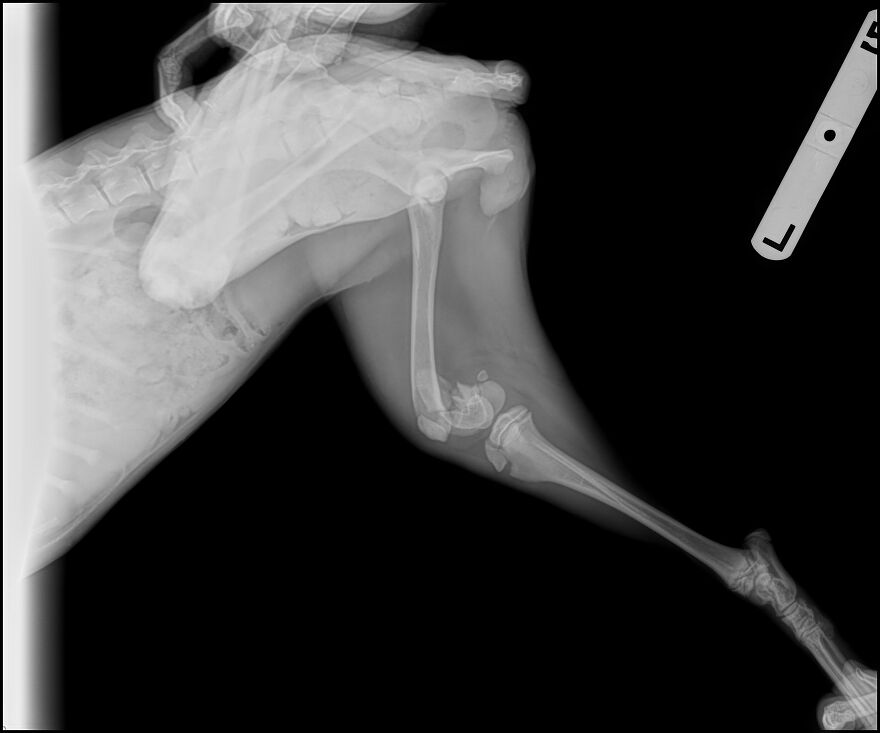

Her guardian, who describes Jazz as their best friend and constant companion, rushed her to the vet for x-rays and an emergency consult. The news was devastating, with results showing surgery is urgent, and the estimated cost is $4,000. Without the funds or eligibility for care credit, Jazz’s person faced an impossible choice.